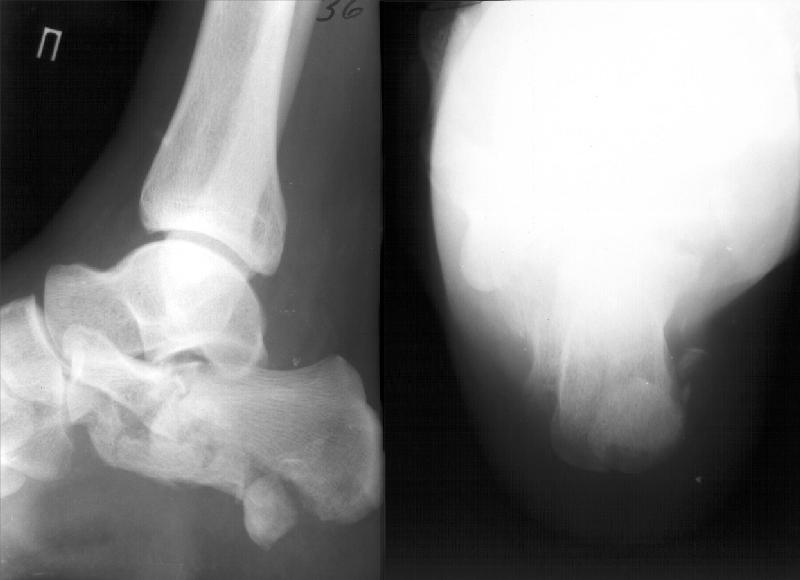

Стандартные проекции не дают полной информации о тяжести повреждения таранно-пяточного сустава.

Решая вопрос о возможности реконструкции необходимо выполнение компьютерной томографии, которая даст ясную картину тяжести повреждения сустава (два фрагмента или несколько) и соответственно спланировать реконструкцию.

Закрытая репозиция маловероятно восстановит конгруэтность суставной поверхности , лигаментотаксис эффективен при 1 и 2 типах переломов пяточной кости( Essex Lopresti классиф)

3 тип требует открытой репозиции. На томограммах при таком типе перелома суставная поверхность расколота на два или 3 фрагмента с импакцией

латерального или промежуточного(при многооскольчатом характере перелома) фрагментов (split-depression). Оптимальное время для вмешательства первые 24 часа после травмы(пока отек не успел нарасти) или после недели, двух, когда отек уже спал критерий -wrinkle test - появление *морщин* в области пятки.

Как раз два дня назад прооперировали перелом пяточной кости, стандартные ренгенограммы не выглядели столь драматично как в вашем случае, но

томограммы рассеяли все сомнения в отношении необходимости открытой репозиции. Попытаюсь еще раз отправить снимки ( первый раз сервер все вернул назад - размер послания оказался больше пропускного)

Попытаюсь отправить снимки перелома пяточной кости в разбивку.

КТ.